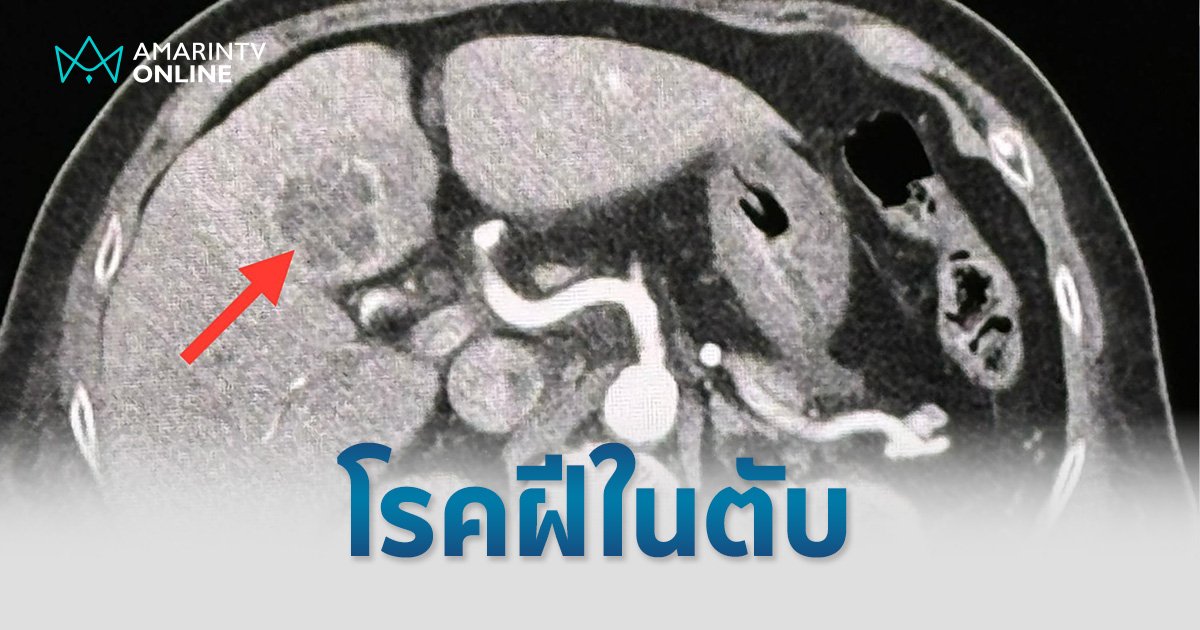

เจาะเลือด เม็ดเลือดขาวในเลือดสูง 29,300 ค่าเอนไซม์ตับสูงเล็กน้อย SGOT 87, SGPT 73 ทำอัลตราซาวด์ช่องท้องด้านบน พบก้อนในตับข้างซ้ายขนาด 2.8 × 2.4 × 2.4 เซนติเมตร ส่งเลือดเพาะเชื้อ ขึ้นเชื้อแบคทีเรีย Klebsiella pneumoniae ทำคอมพิวเตอร์ช่องท้อง 2 วันต่อมา พบก้อนขนาด 3.3 × 3.3 × 2.8 ซม.ในตับข้างซ้าย เข้าได้กับฝีในตับ

วินิจฉัย ฝีในตับจากเชื้อแบคทีเรีย Klebsiella pneumoniae และติดเชื้อในกระแสเลือด ทำให้ช็อก ความดันต่ำ